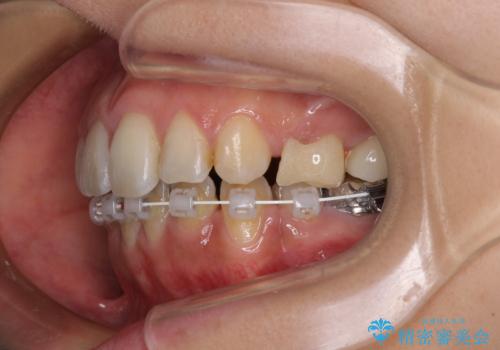

デコボコと口元の突出感 ハーフリンガルでの抜歯矯正

- 矯正装置

- ハーフリンガル

- 前歯のデコボコと上顎の前突感による口の閉じにくさを気にして来院された患者様です。

目立たない装置を希望されたので、上顎が裏側装置のハーフリンガルを選択し、上下左右の小臼歯(計4歯)を抜歯して矯正治療を行うこととしました。

表側のワイヤー矯正に比べると治療期間は長く、費用も高額となりますが、どうしても目立たせたくないという方にはお勧めの抜歯矯正です。